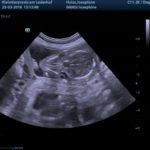

Sie wurde zur Sicherheit noch einmal geschallt weil sie seit ein paar Tagen Ausfluss hat.

Es ist aber alles in Ordnung und die Föten sind putzmunter.

Tag 47 der Trächtigkeit

Die Föten sehen nun aus wie Hunde. Kopf und Rumpf sind unterscheidbar. Das Geschlecht ist bestimmbar.(Tag 35) Die Fellfarbe beginnt sich zu entwickeln. Der Herzschlag der Föten ist per Stetoskop hörbar.